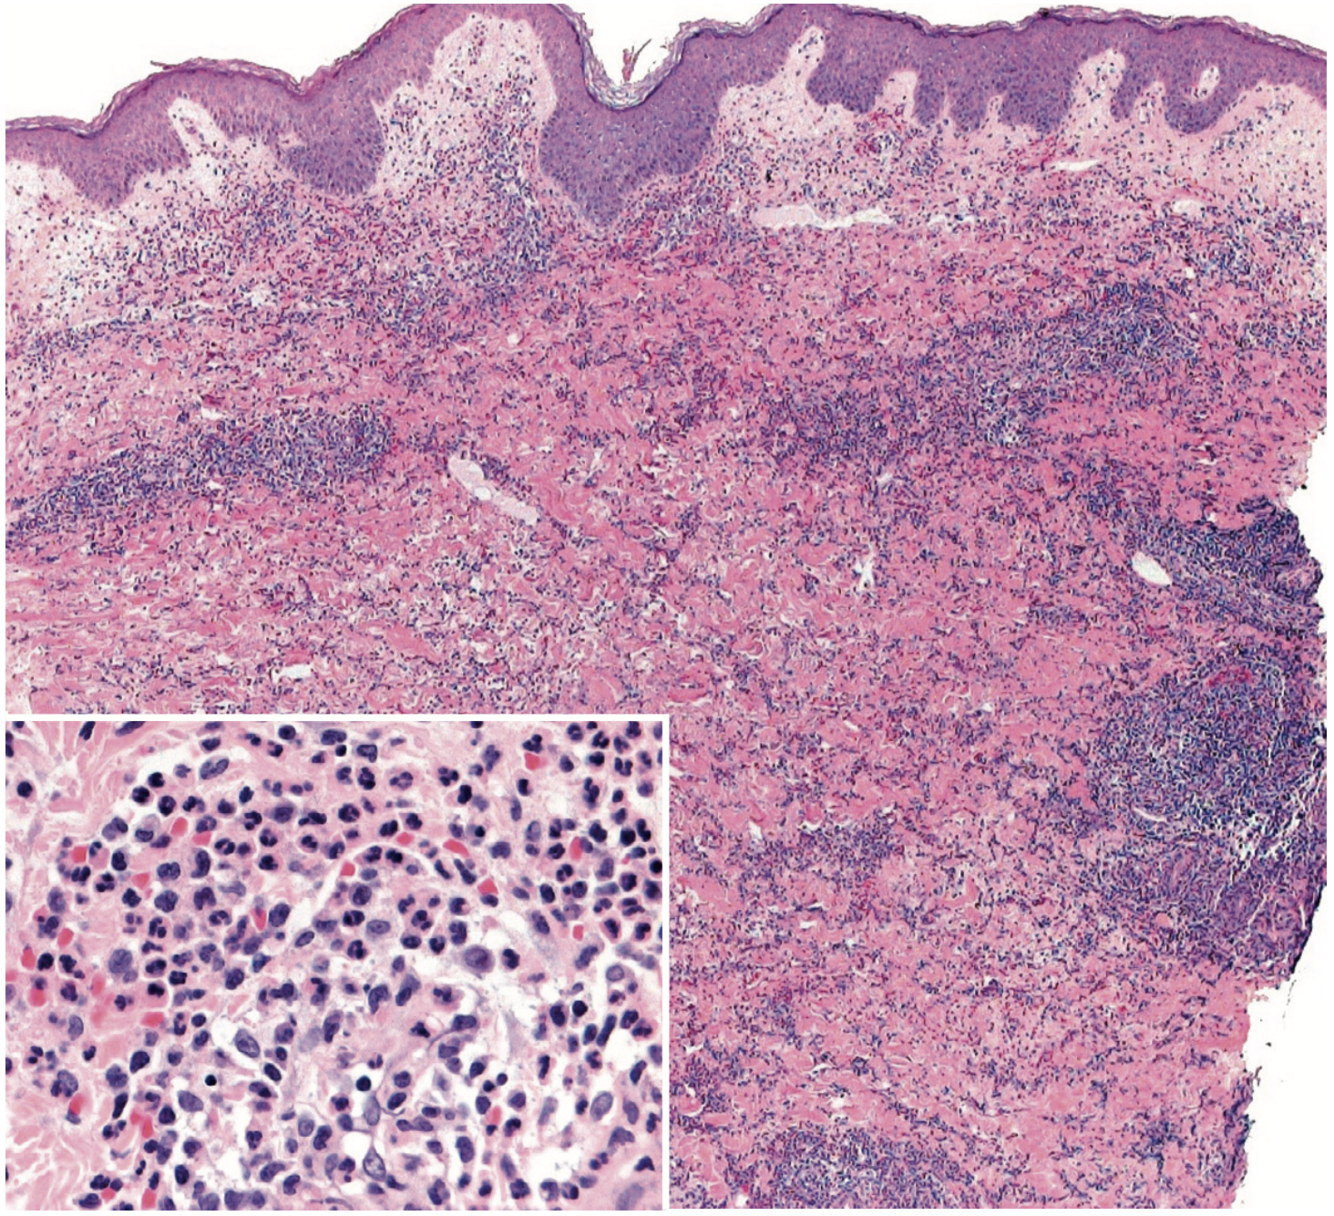

Histologie Sweet

Infiltrat neutrophilique dense

nodulaire

périvasculaire

parfois extension SC (panniculite septale > lobulaire)

Oedème

Parfois bulles ou pustules sous-cornéennes

Leucocytoclasie sans vasculite (ou minime)

oedème endothélial

pas de nécrose fibrinoïde

Variantes

Hystiocytoïde

infiltrat dermique, parfois SC, de cellules myéloïdes immatures histiocytes-like

DDx leucémie cutis

Lymphocytaire

association avec SMD

Éosinophilique